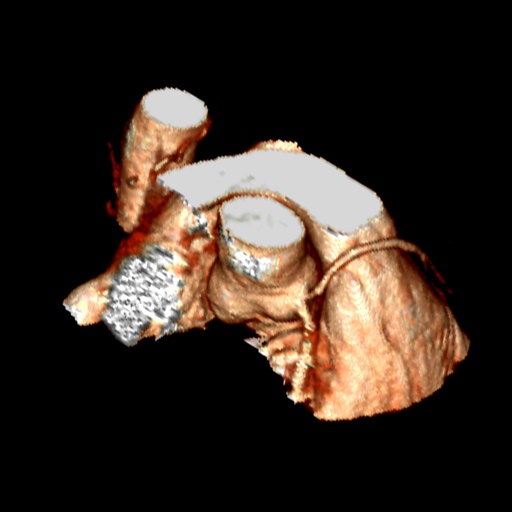

Νέα γυναίκα με μονήρη στεφανιαία αρτηρία, NSVT και συγκοπή

Κλινικά στοιχεία

35χρονη γυναίκα, η οποία παρουσιάσθηκε με συγκοπή [οι περιστάσεις ήταν συμβατές με νευραγγειακή διαταραχή]. Στο Holter, όμως, βρέθηκε μη-εμμένουσα κοιλιακή ταχυκαρδία, και γι’ αυτό ξεκίνησε τυποποιημένη διερεύνηση.

CTA στεφανιογραφία και ΜRI